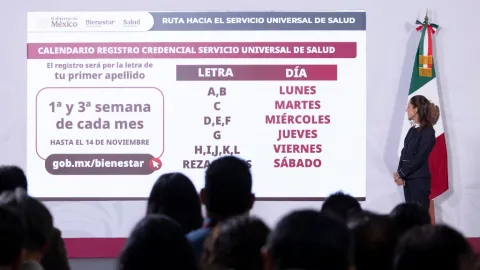

México Lanza Servicio Universal de Salud desde Enero 2027 con Credencial Única